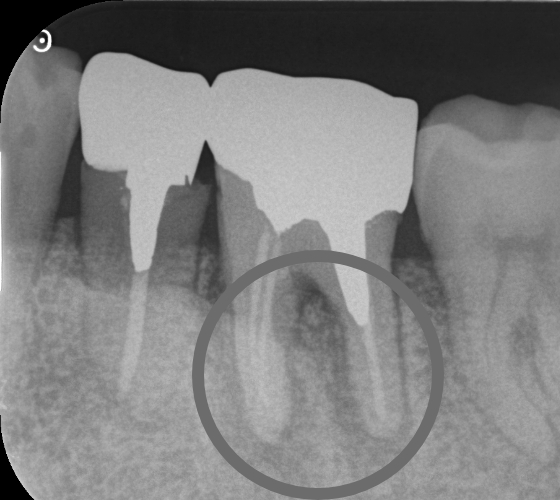

治療内容 以前他院で根管治療(根の治療)をした歯が、歯肉の腫れと排膿(膿が出る)や痛みが再発した症例です。

レントゲン写真で根尖部(根の先)に明らかな透過像(病変)を認めたため、再根管治療(根の治療)を行いました。

マイクロスコープ(顕微鏡)を用いて、ラバーダム防湿下で根管内を徹底洗浄・消毒後、根管を緊密に再封鎖しました。

治療後は腫れや痛みが速やかに消失し、レントゲン上でも根尖部(根の先)の透過像(病変)が著しく縮小したのを確認しました。